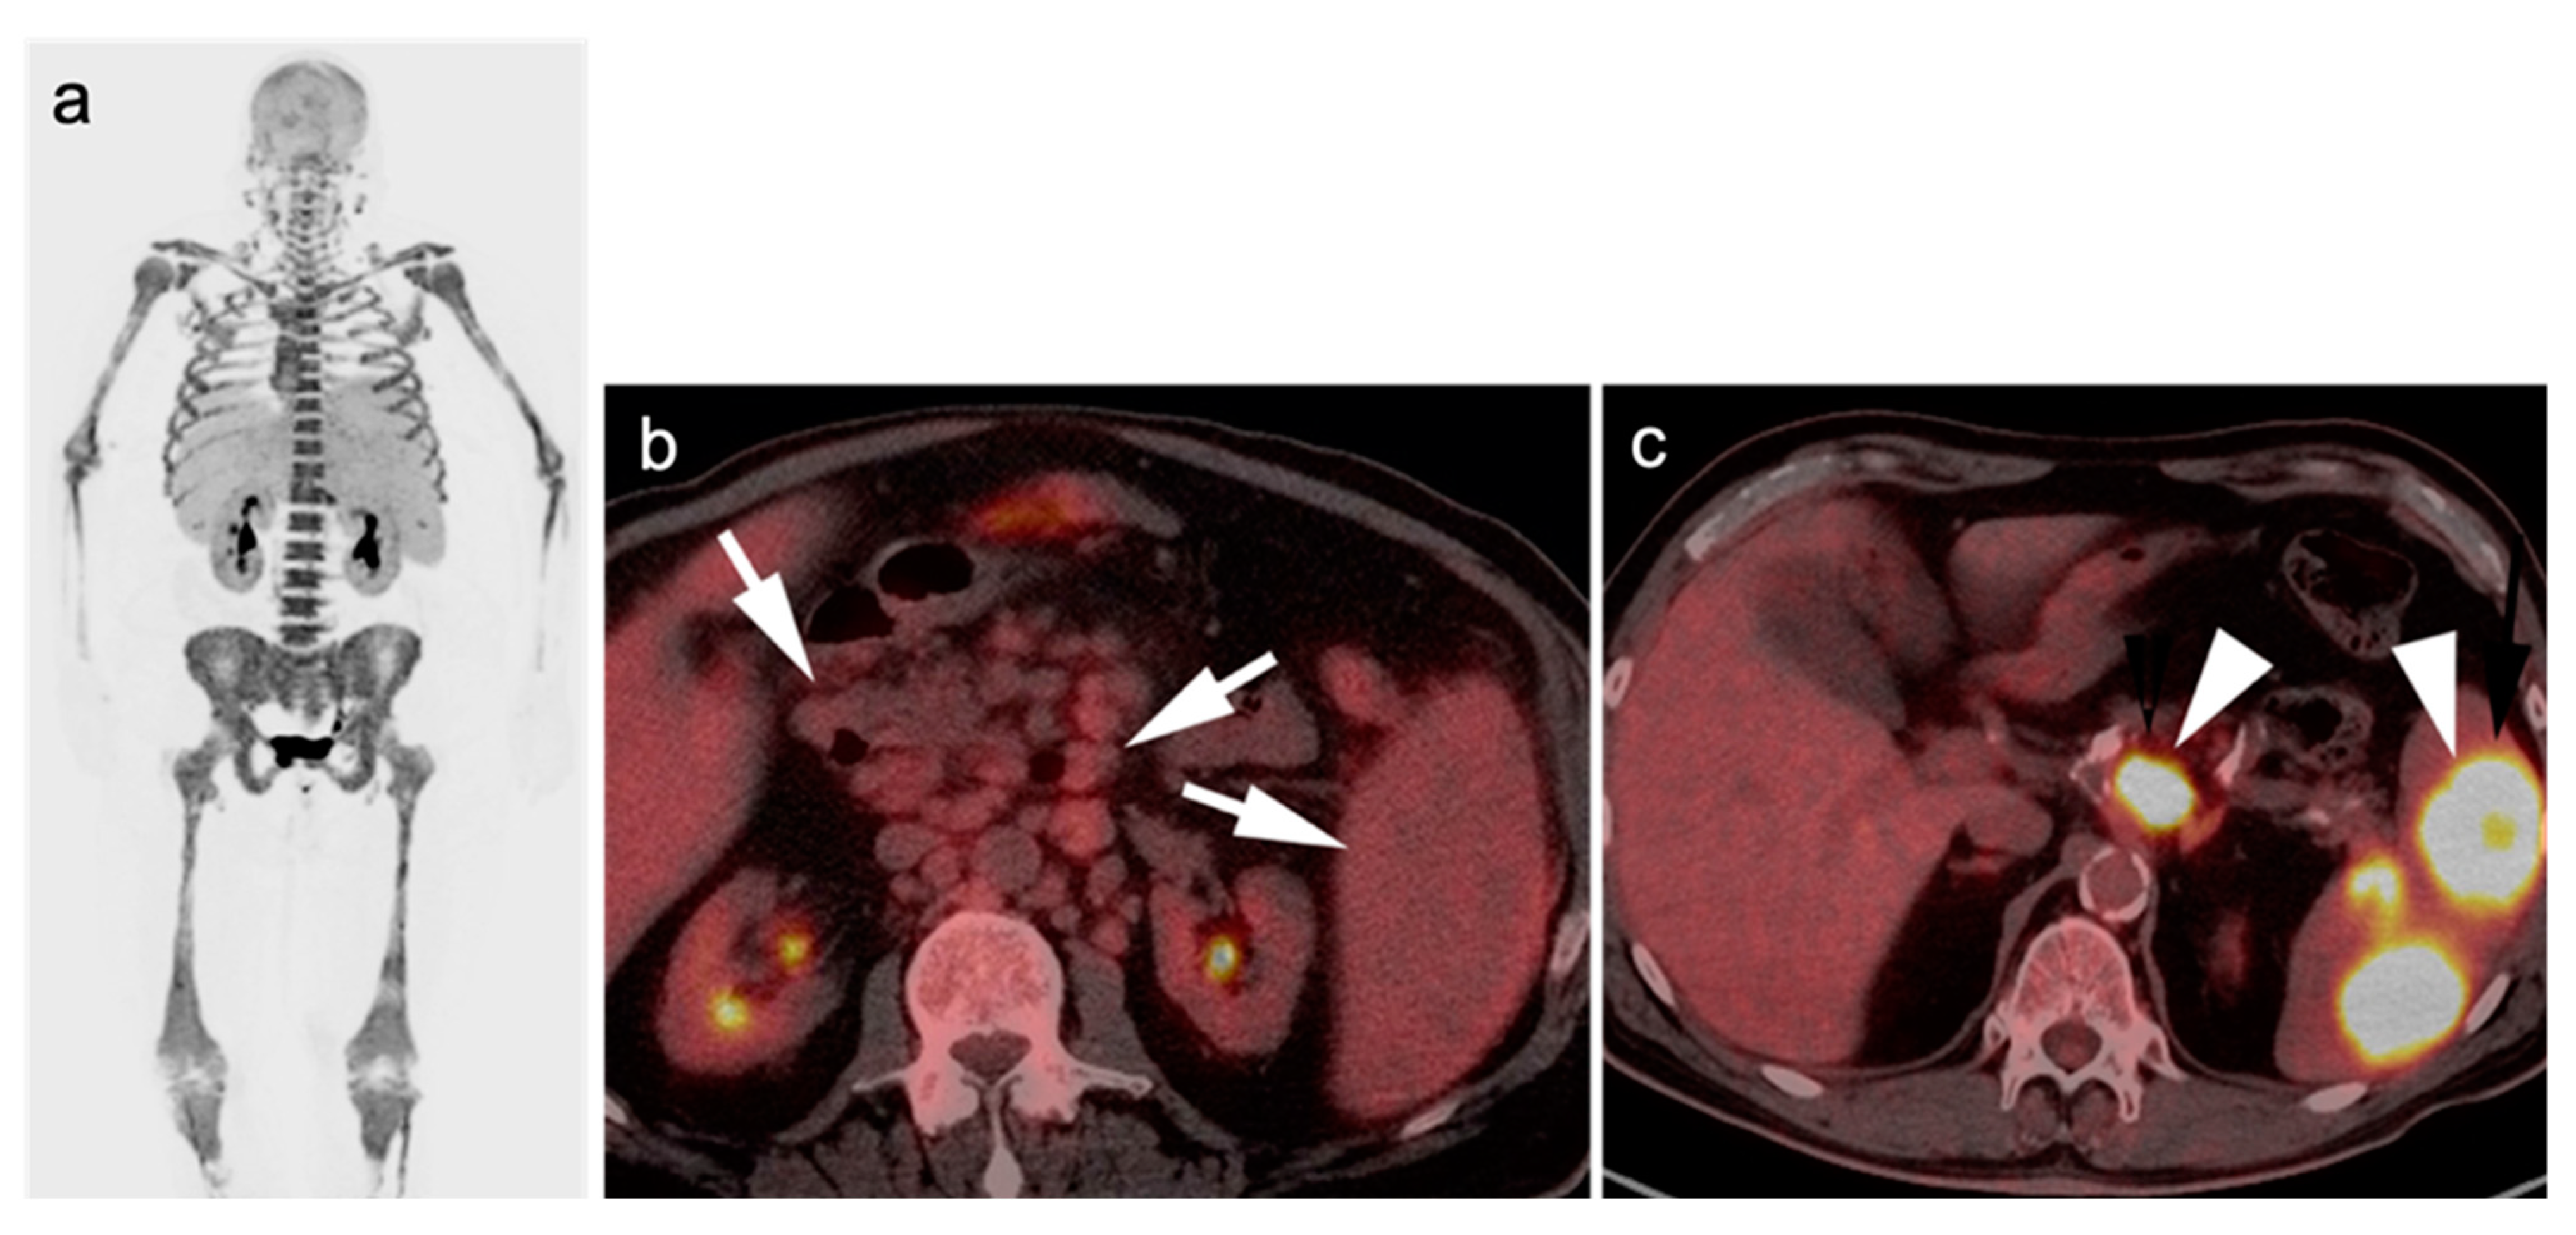

2.2.3. Baseline FDG PET-CT for Staging Lymphoma

2.3.2. Follicular Lymphoma (FL)

- Kashyap, R.; Rai Mittal, B.; Manohar, K.; Balasubramanian Harisankar, C.N.; Bhattacharya, A.; Singh, B.; Malhotra, P.; Varma, S. Extranodal manifestations of lymphoma on [¹⁸F]FDG-PET/CT: A pictorial essay. Cancer Imaging 2011, 11, 166–174. [Google Scholar] [CrossRef]

- Mueller, P.R.; Ferrucci JTJr Harbin, W.P.; Kirkpatrick, R.H.; Simeone, J.F.; Wittenberg, J. Appearance of lymphomatous involvement of the mesentery by ultrasonography and body computed tomography: The “sandwich sign”. Radiology 1980, 134, 467–473. [Google Scholar] [CrossRef] [PubMed]